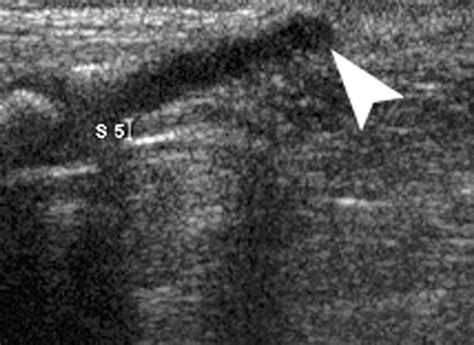

• Imaging Studies: X-rays, MRI, or CT scans to visualize the spinal cord and surrounding structures.

• Ultrasound: To assess for the presence of cysts or other abnormalities.